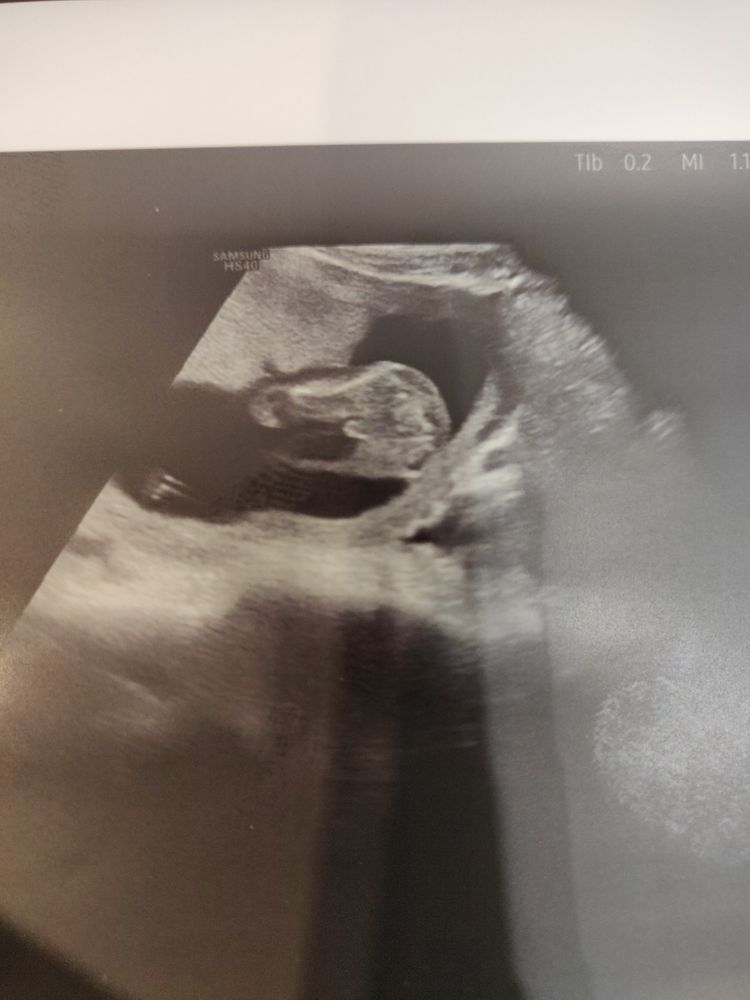

Девочки милые помогите!🤗🥺

Мальчишка) такую же картину сегодня видела)

Ну слушайте, я вижу уже стручок, у девули все-таки пирожочек там) Похоже, что мальчишка)

Тут точно пацан 😁

Alisa, точно))) мои мальчишки так же выглядели на узи 😁

Alisa, у меня 3 дочки ,сейчас сына жду ...поверьте у девочек такого меж ножек нет

Пацан, тут ни с чем не спутать мне кажется))))

Пфф.. у меня младший сын всю беременность ногой прижимал свое хозяйство так, что по УЗИ все ставили мне девочку)) Но у вас тут невооружённым взглядом видно, что молодой человек 💪

Да парень 100%💙 У девочек такого не бывает.

Мальчишка это. У девочек по-другому всё выглядит)